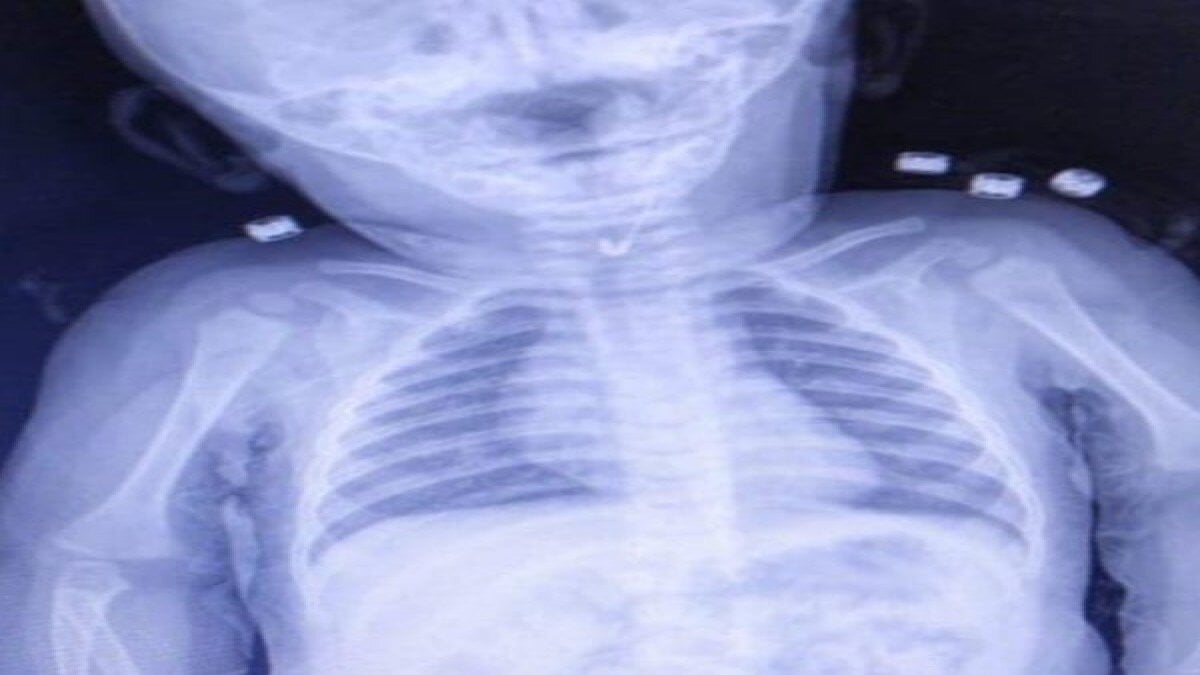

Bebeği muayene eden Gastroenterolojik Cerrahi Uzmanı Dr. İhsan Gündüz ve Anestezi Uzmanı Dr. İbrahim Çetin, yabancı cisim yutulmasından şüphe ederek röntgen istedi.

YEMEK BORUSUNDAN ÇENGELLİ İĞNE ÇIKTI

Çekilen röntgende, bebeğin çengelli iğne yuttuğu tespit edildi. Bebeğin yemek borusuna saplanan iğne, endoskopik yöntemle çıkarıldı. Hastane Başhekimi Aykut Demirkıran, bebeğin sağlık durumunun iyi olduğunu belirtti.